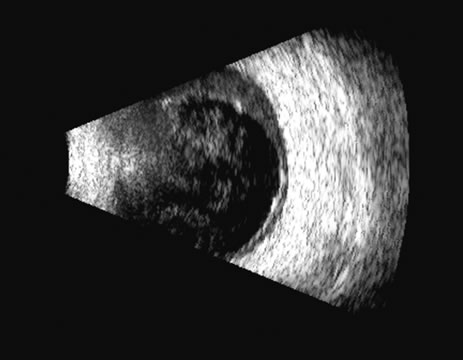

On B-scan, the invasion or replacement of the choroid by tumor is of diagnostic importance. Subretinal hemorrhage rests on a smooth curve of the posterior poles; whereas melanoma may replace the choroid, producing an “excavated” pattern.36 A completely dislocated lens can also emulate a tumor but can be differentiated by clinical findings and by having the patient move his or her eye during the examination, which causes lens displacement (Fig. 24).

Fig. 24. In this traumatized eye, the crystalline lens was completely dislocated and can be seen as a rounded mass in the posterior chamber, in a suitable plane.